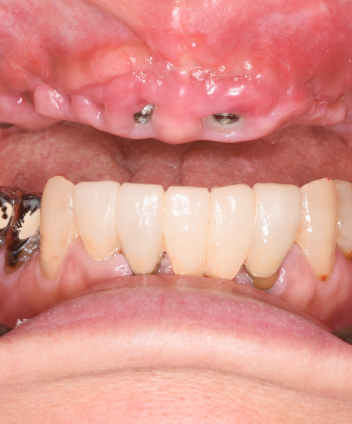

Treatment Case

Treatment

Case